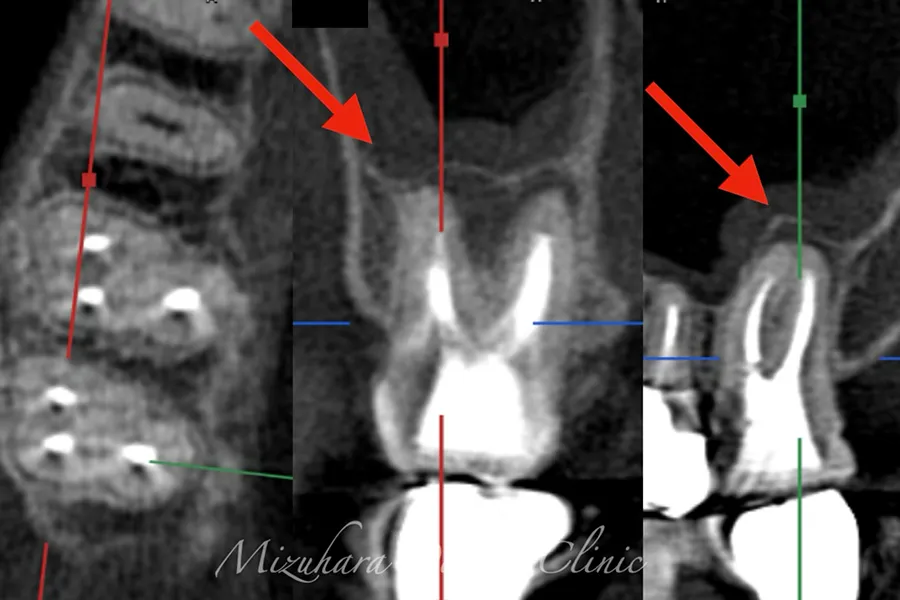

予知性の高い治療を提供できるだけ患者様の大切な歯を残し、10年、20年先まで健康な状態を保てるよう、長期的な視点で治療を計画します。そのために最も重要なのが、「診査」と「診断」です。的確な診断は精密な診査から生まれ、治療結果を大きく左右します。問診や簡易検査だけでは見逃されがちな病変も、CTやマイクロスコープなどの最新の医療機器を活用し、時間をかけて丁寧に「診査・診断」を行います。

世界基準の成功率を目指した精密根管治療

根管治療

当院では豊マイクロスコープ、ラバーダムを使用し、世界基準の成功率を目指した精密根管治療による「歯を残す」ための治療をご提供します。